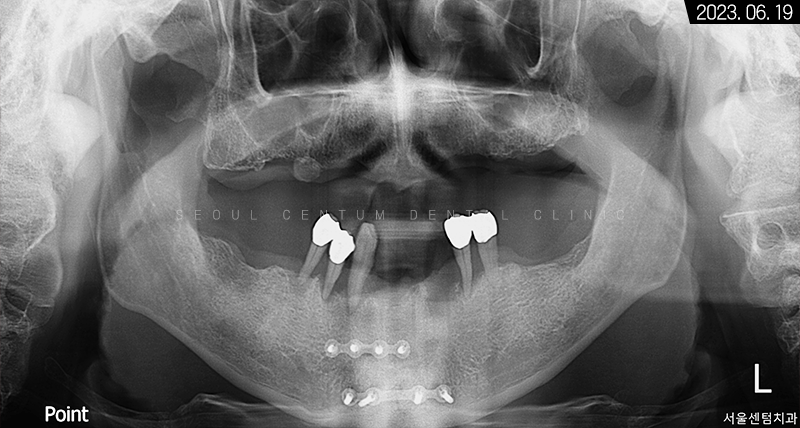

파노라마 엑스레이 사진을 보면 뿌리 주변이 골 소실로 인해 까맣다는 것을 확인할 수 있습니다.

보존해서 쓴다고 해도 1~2년 후에 자연 탈락할 가능성이 높아 조속하게 발치 후 임플란트를 진행하는 것이 적합하다고 판단이 들었습니다.

3개월이 더 지난 후 치근단 사진과 파노라마 엑스레이 사진으로 살펴봐도 초기 임플란트 식립 상황과 동일하게 견고히 자리 잡아 있는 것을 볼 수 있었습니다. 주위염도 생기지 않아 이상적인 결과를 만들어볼 수 있었어요.